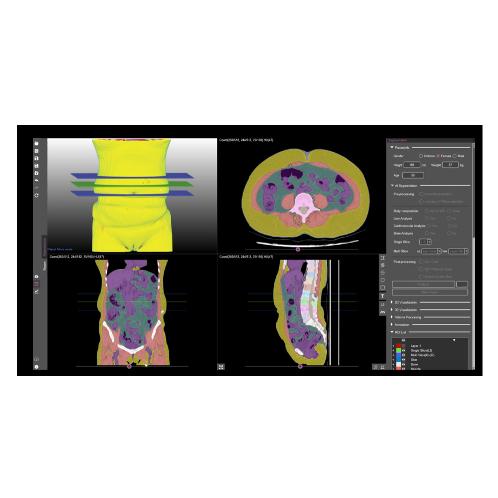

MEDICAL IP DeepCatch

- Brand :

- DeepCatch

- MOQ :

- 1 ea

USD 70,000.00 -

MEDICAL IP, MEDICAL IP DeepCatch, CT body Composition,AI Software,Opportunistic Screening, CT body Composition,AI Software,Opportunistic Screening

- Brand :

- DeepCatch

- Size :

- AI Solution

- MOQ :

- 1 ea

USD 70,000.00MEDICAL IP- Business Type

- Manufacturer

- Main Product

- MEDIP PRO, DeepCatch, TiSepX, MDBOX, ANATDEL